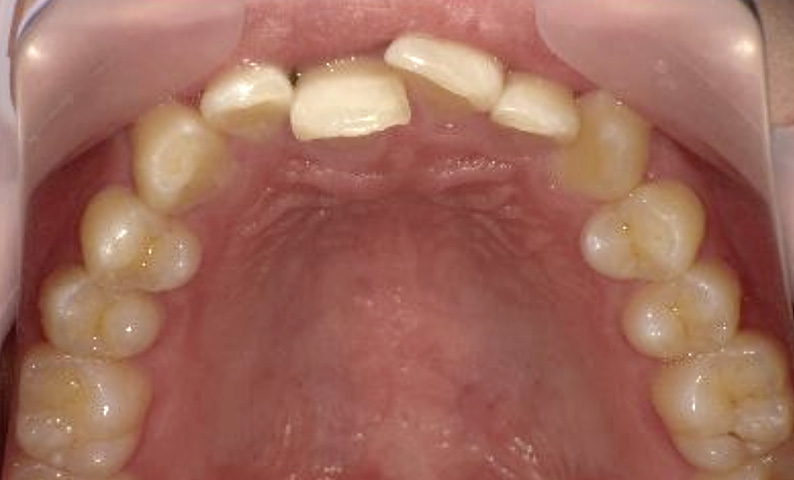

症例_021 上顎だけの部分矯正

治療期間:8ヶ月金額:30万円+税女性前歯のガタガタ八重歯上の前歯だけ

| Before | After |